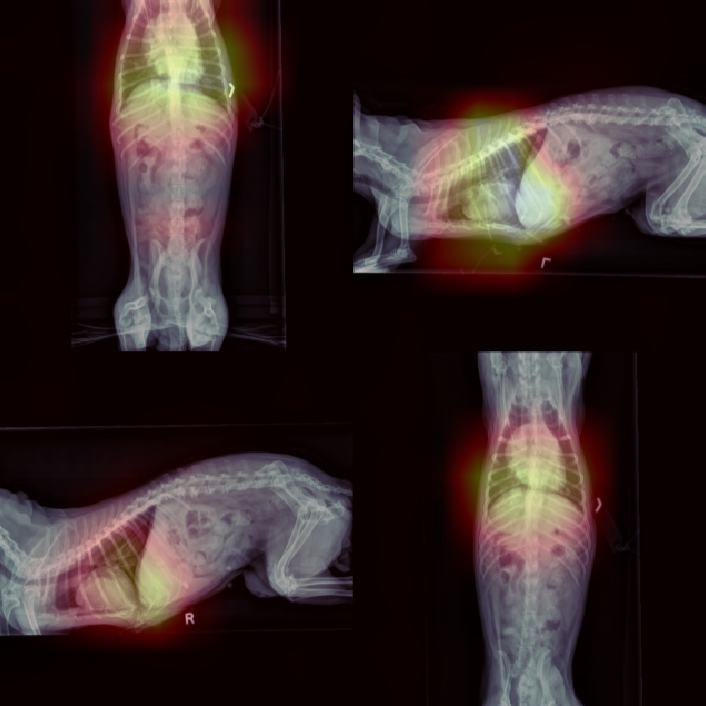

This section presents visualizations of the Vision Transformer (ViT) attention maps. The ViT used is specific to lung diseases, and the attention maps are shown for patients with the positive label ’Pulmonary Mass’. The input to the ViT is a concatenated feature map, and the X-ray images have been mapped and displayed with the same concatenation and transformations applied to the augmented feature maps.

The attention maps show that the ViT focuses on the thorax region where the lungs are located, as expected. The results also demonstrate that the ViT remains focused on the thorax area even with different contexts in the X-ray images. This highlights the robustness of ViTs.